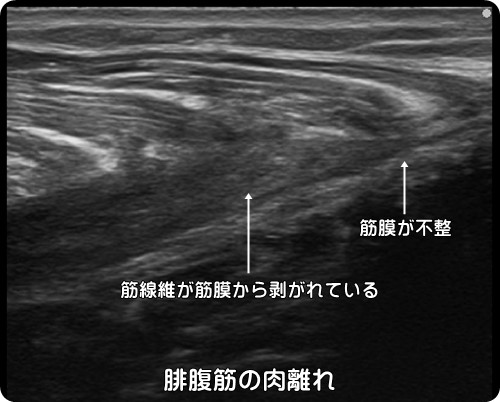

肉離れの超音波エコー画像

下図の肉離れでは腓腹筋が筋膜から剥がれ、出血し黒い血腫(けっしゅ)が確認できます。

筋膜も損傷するために綺麗に描出されません。